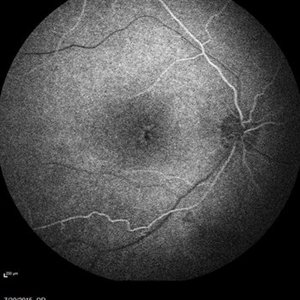

Retinal Dystrophy of 24-Year-Old Male/ AF OD

Nov 25 2015 by Zach Dupureur

Fluorescein angiography of a 24-year-old male. Juvenile retinoschisis on OCT. FA shows outer retinal staining. Could be associated with Goldman Farve Syndrome.

Photographer: Zach Dupureur OCT-C

Imaging device: Heidelberg Spectralis

Condition/keywords: Goldmann-Favre Syndrome, juvenile retinoschisis, retinal dystrophy